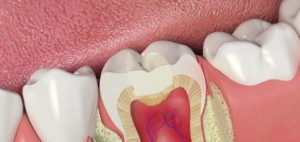

Рис. 2. Этапы лечения и пломбировки каналов (схема) – почему болит зуб?

Дело в том, что причиной возникновения боли после лечения чаще всего бывает не сам зуб, а медленно проходящий воспалительный процесс в тканях, которые расположены вокруг зуба и окружают его со всех сторон – это ткани пародонта, надкостница челюсти, слизистая оболочка десны или связка зуба. Постепенно, по мере регресса воспаления и заживления тканей, боль полностью проходит. Поэтому если зуб болит после пломбирования, паниковать не стоит, лучше еще раз обратиться к своему врачу и в случае необходимости сделать рентгеновский снимок или ортопантомограмму.

Если болит зуб без нерва, то причины хорошо известны и уже описаны выше. В таких случаях речь идет о том, что болит уже не сам зуб, а болят воспаленные ткани, расположенные вокруг пролеченного зуба.